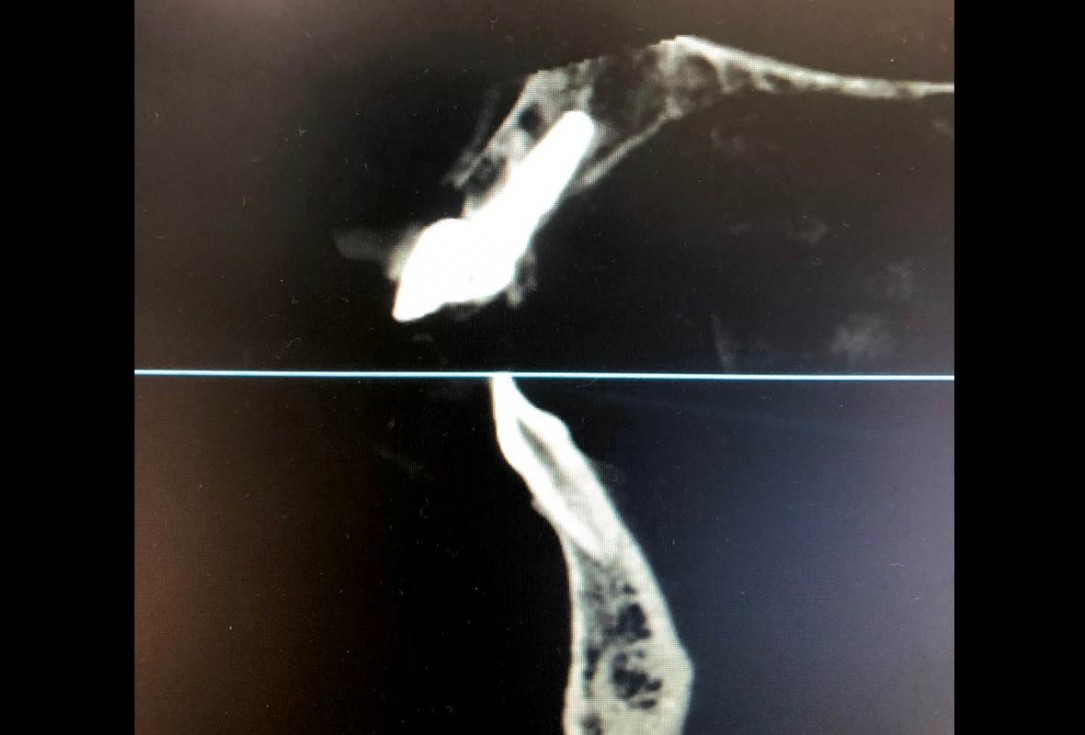

01/22 - Initial clinical situation - Central incisors with dental destruction and periapical pathologycerabone® and mucoderm® for immediate implantation in the aesthetic area - Dr. D. Robles

02/22 - Initial clinical situation - Central incisors with dental destruction and periapical pathologycerabone® and mucoderm® for immediate implantation in the aesthetic area - Dr. D. Robles